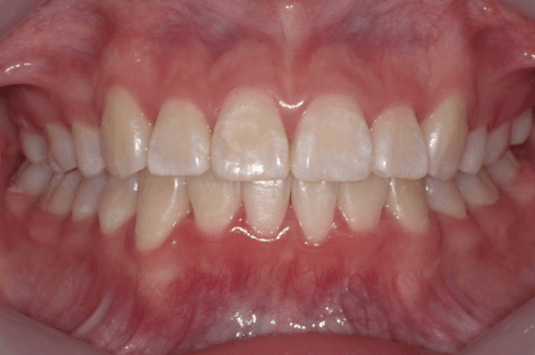

●7か月後

前歯部のトルクコントロール、上下顎の正中の一致、犬歯関係、大臼歯関係が良好になり、咬合関係が改善。(写真c)